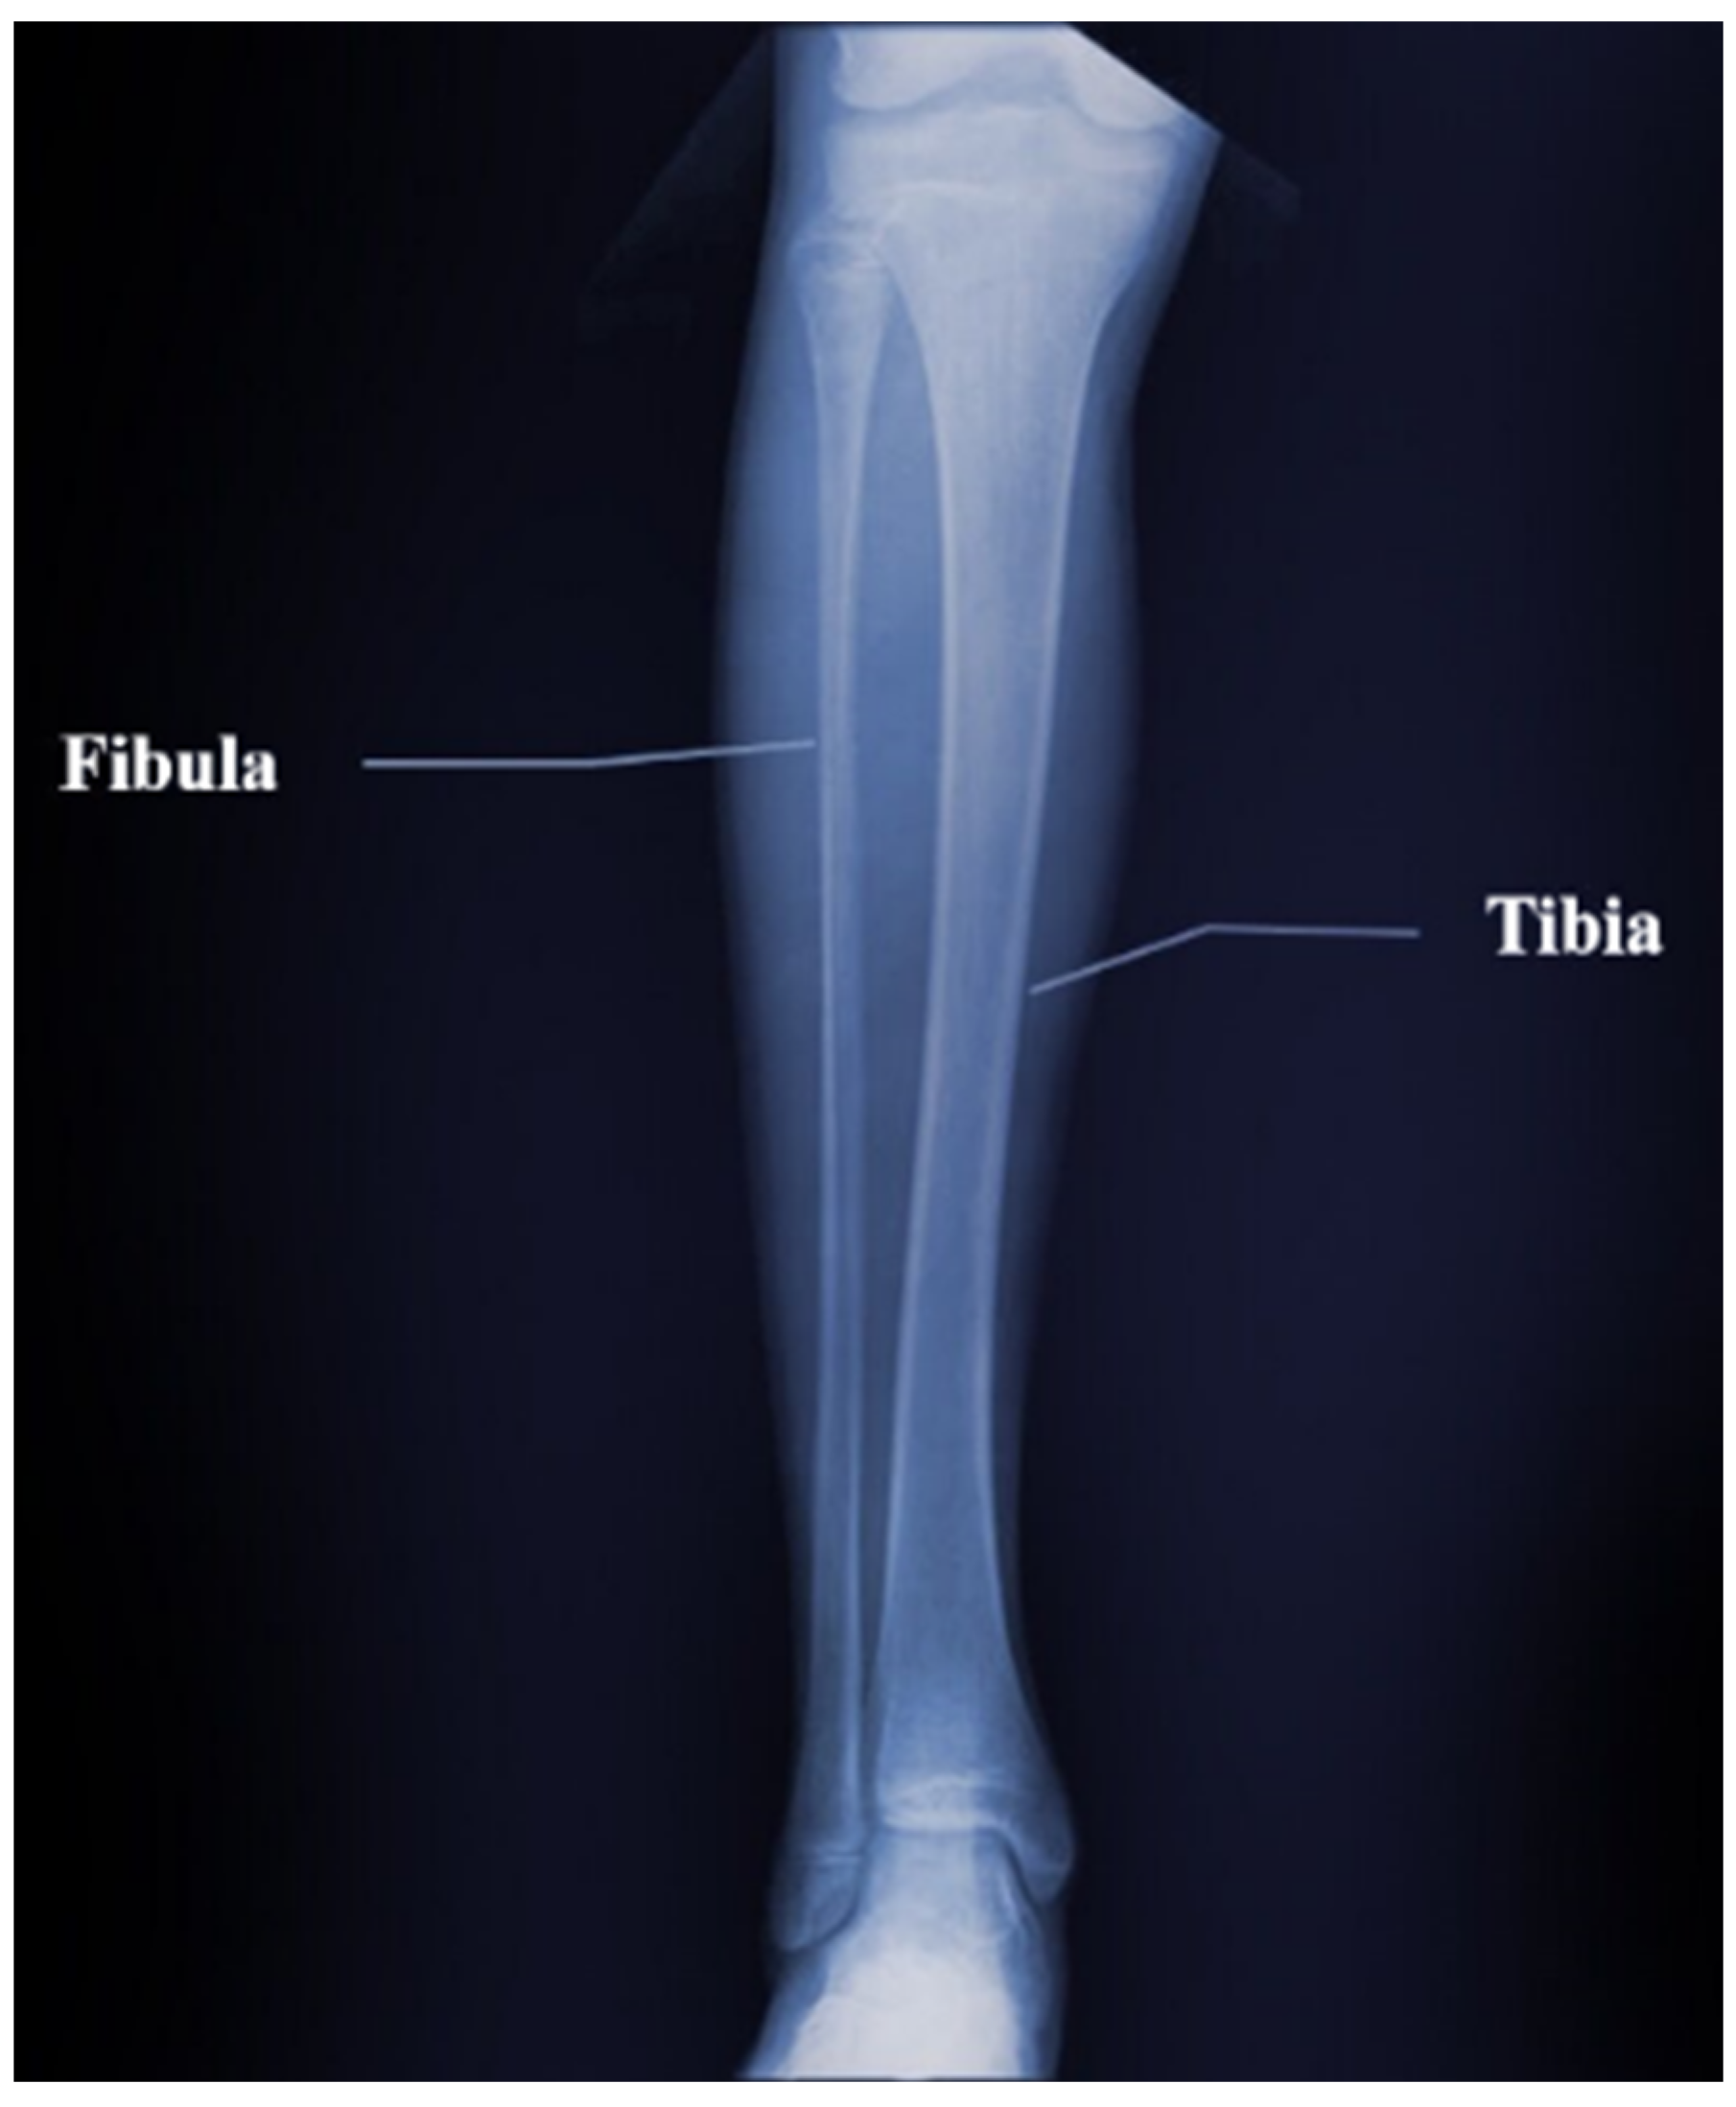

3.5. Inversion Results of the Tibia and Fibula Model

The tibia is an important bone in the calf that supports the weight of the body while the fibula is attached to the calf muscles and bears one-sixth of body weight. The two bones are connected as one by the superior tibia–fibula joint and the inferior tibia–fibula joint, and they are important bones in human BMD measurements. As shown in Figure 30, we selected a segment in the middle of the tibia–fibula pair as an objective model to better validate the extensiveness of our modified FWI algorithm. The approximate objective model is as follows:

Structure of the tibia–fibula bone pair.

As in Figure 31, the deep-red color represents the velocity and density of bone tissues, set at 3500 m/s and 1800 kg/m3, respectively. The blue regions represents the surrounding soft tissues of the bone, and the velocity is set at 1500 m/s, and the density is 1000 kg/m3. We present the inversion results in Figure 32. Like the previous results, our method can clearly get the good distribution of the velocity and density parameters of tibia–fibula bone pair model. There are some bad results on the left and right side of the image, because there are more cortical bone structures in the objective model, thus increasing the contrast with the surrounding soft tissue parameters and affecting the inversion results. As before, we can also expand the range of the measurement part in the actual situation and intercept the middle part of the inversion image. Figure 33 shows the row mean relative error and column mean relative error between the inversion model parameters and the objective model parameters. With regard to row mean relative error, the maximum value for velocity error is 0.08, the minimum is close to 0; while for density error, the maximum is 0.04, and the minimum is close to 0. With regard to column mean relative error, the maximum value for velocity error is around 0.04 and the minimum is around 0.03; while the maximum value for density error is around 0.04 and the minimum value is around 0.01. The mean relative error for the obtained velocity is 0.0386, and density is 0.0207.